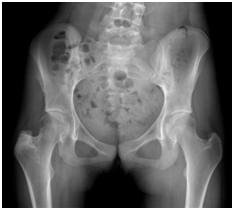

On an elective basis, we surgically removed the lesion followed by curettage and filling with a bone allograft via the lateral approach. The procedure was uncomplicated (Figure 3).

• Figure 3 Removal, curettage and insertion of bone allograft.